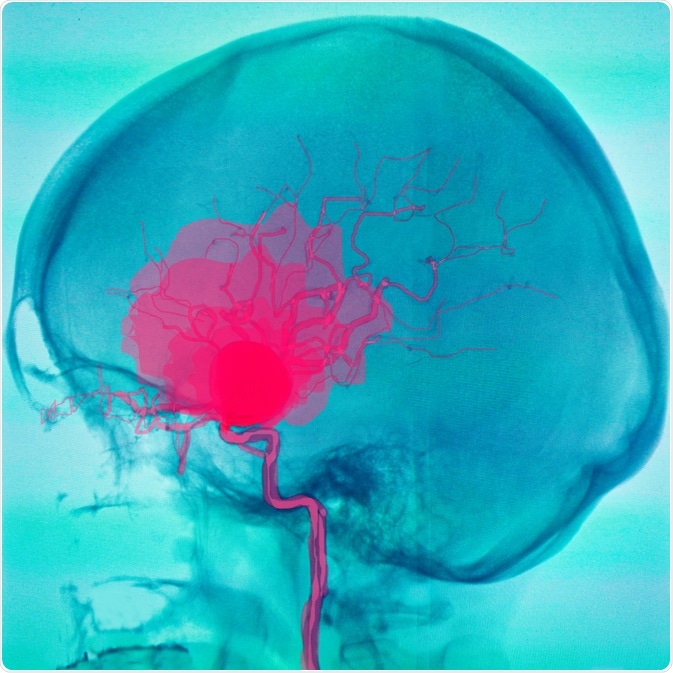

Aneurysm

Image Credit: Semnic/Shutterstock.com